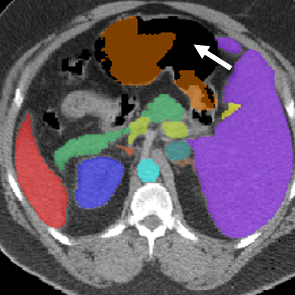

Visualization. We visualize 3D reconstruction results to check what HySparK learns in pre-training. As shown in Fig. 6, our method can almost reconstruct the different shapes of organs, bones, and other details from the very small portion of unmasked patches.

(a)

(b)

(c)

(d)

(e)

(f)